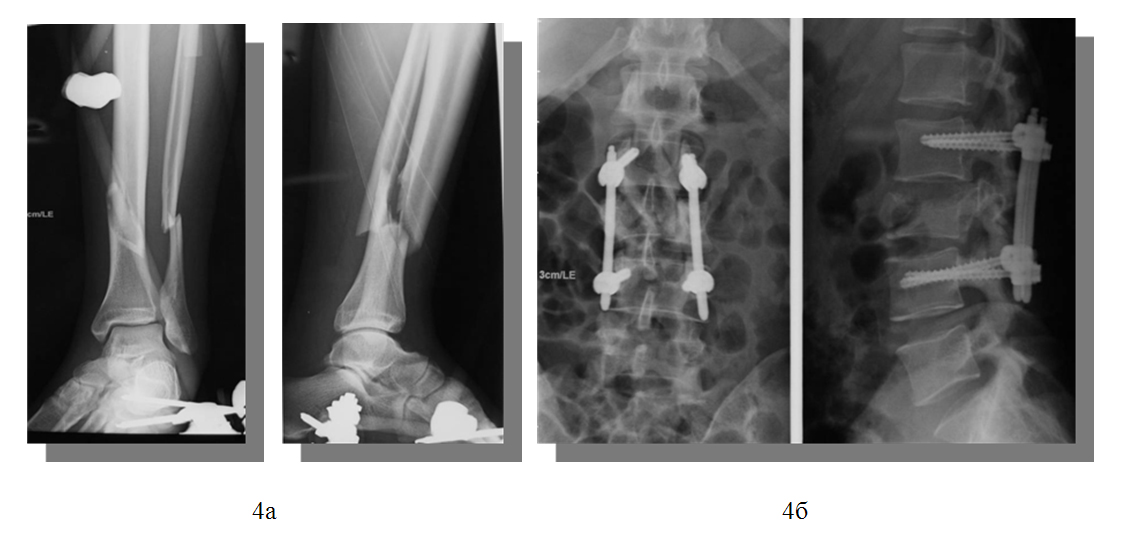

2) закрытый винтообразный перелом нижней трети левой большеберцовой и малоберцовой костей со смещением отломков.

- Закрытая репозиция и остеосинтез левого бедра, голени и стопы стержневым аппаратом «Mefisto» Synthes.

Операция: Репозиция, остеосинтез левой большеберцовой кости интрамедуллярным блокированным штифтом «Expert» Synthes.

Операция: Резекция тела L3 позвонка, передняя декомпрессия корешков спинного мозга, реконструкция позвоночного канала, передний спондилодез кейджем «Synex» с аутокостью.